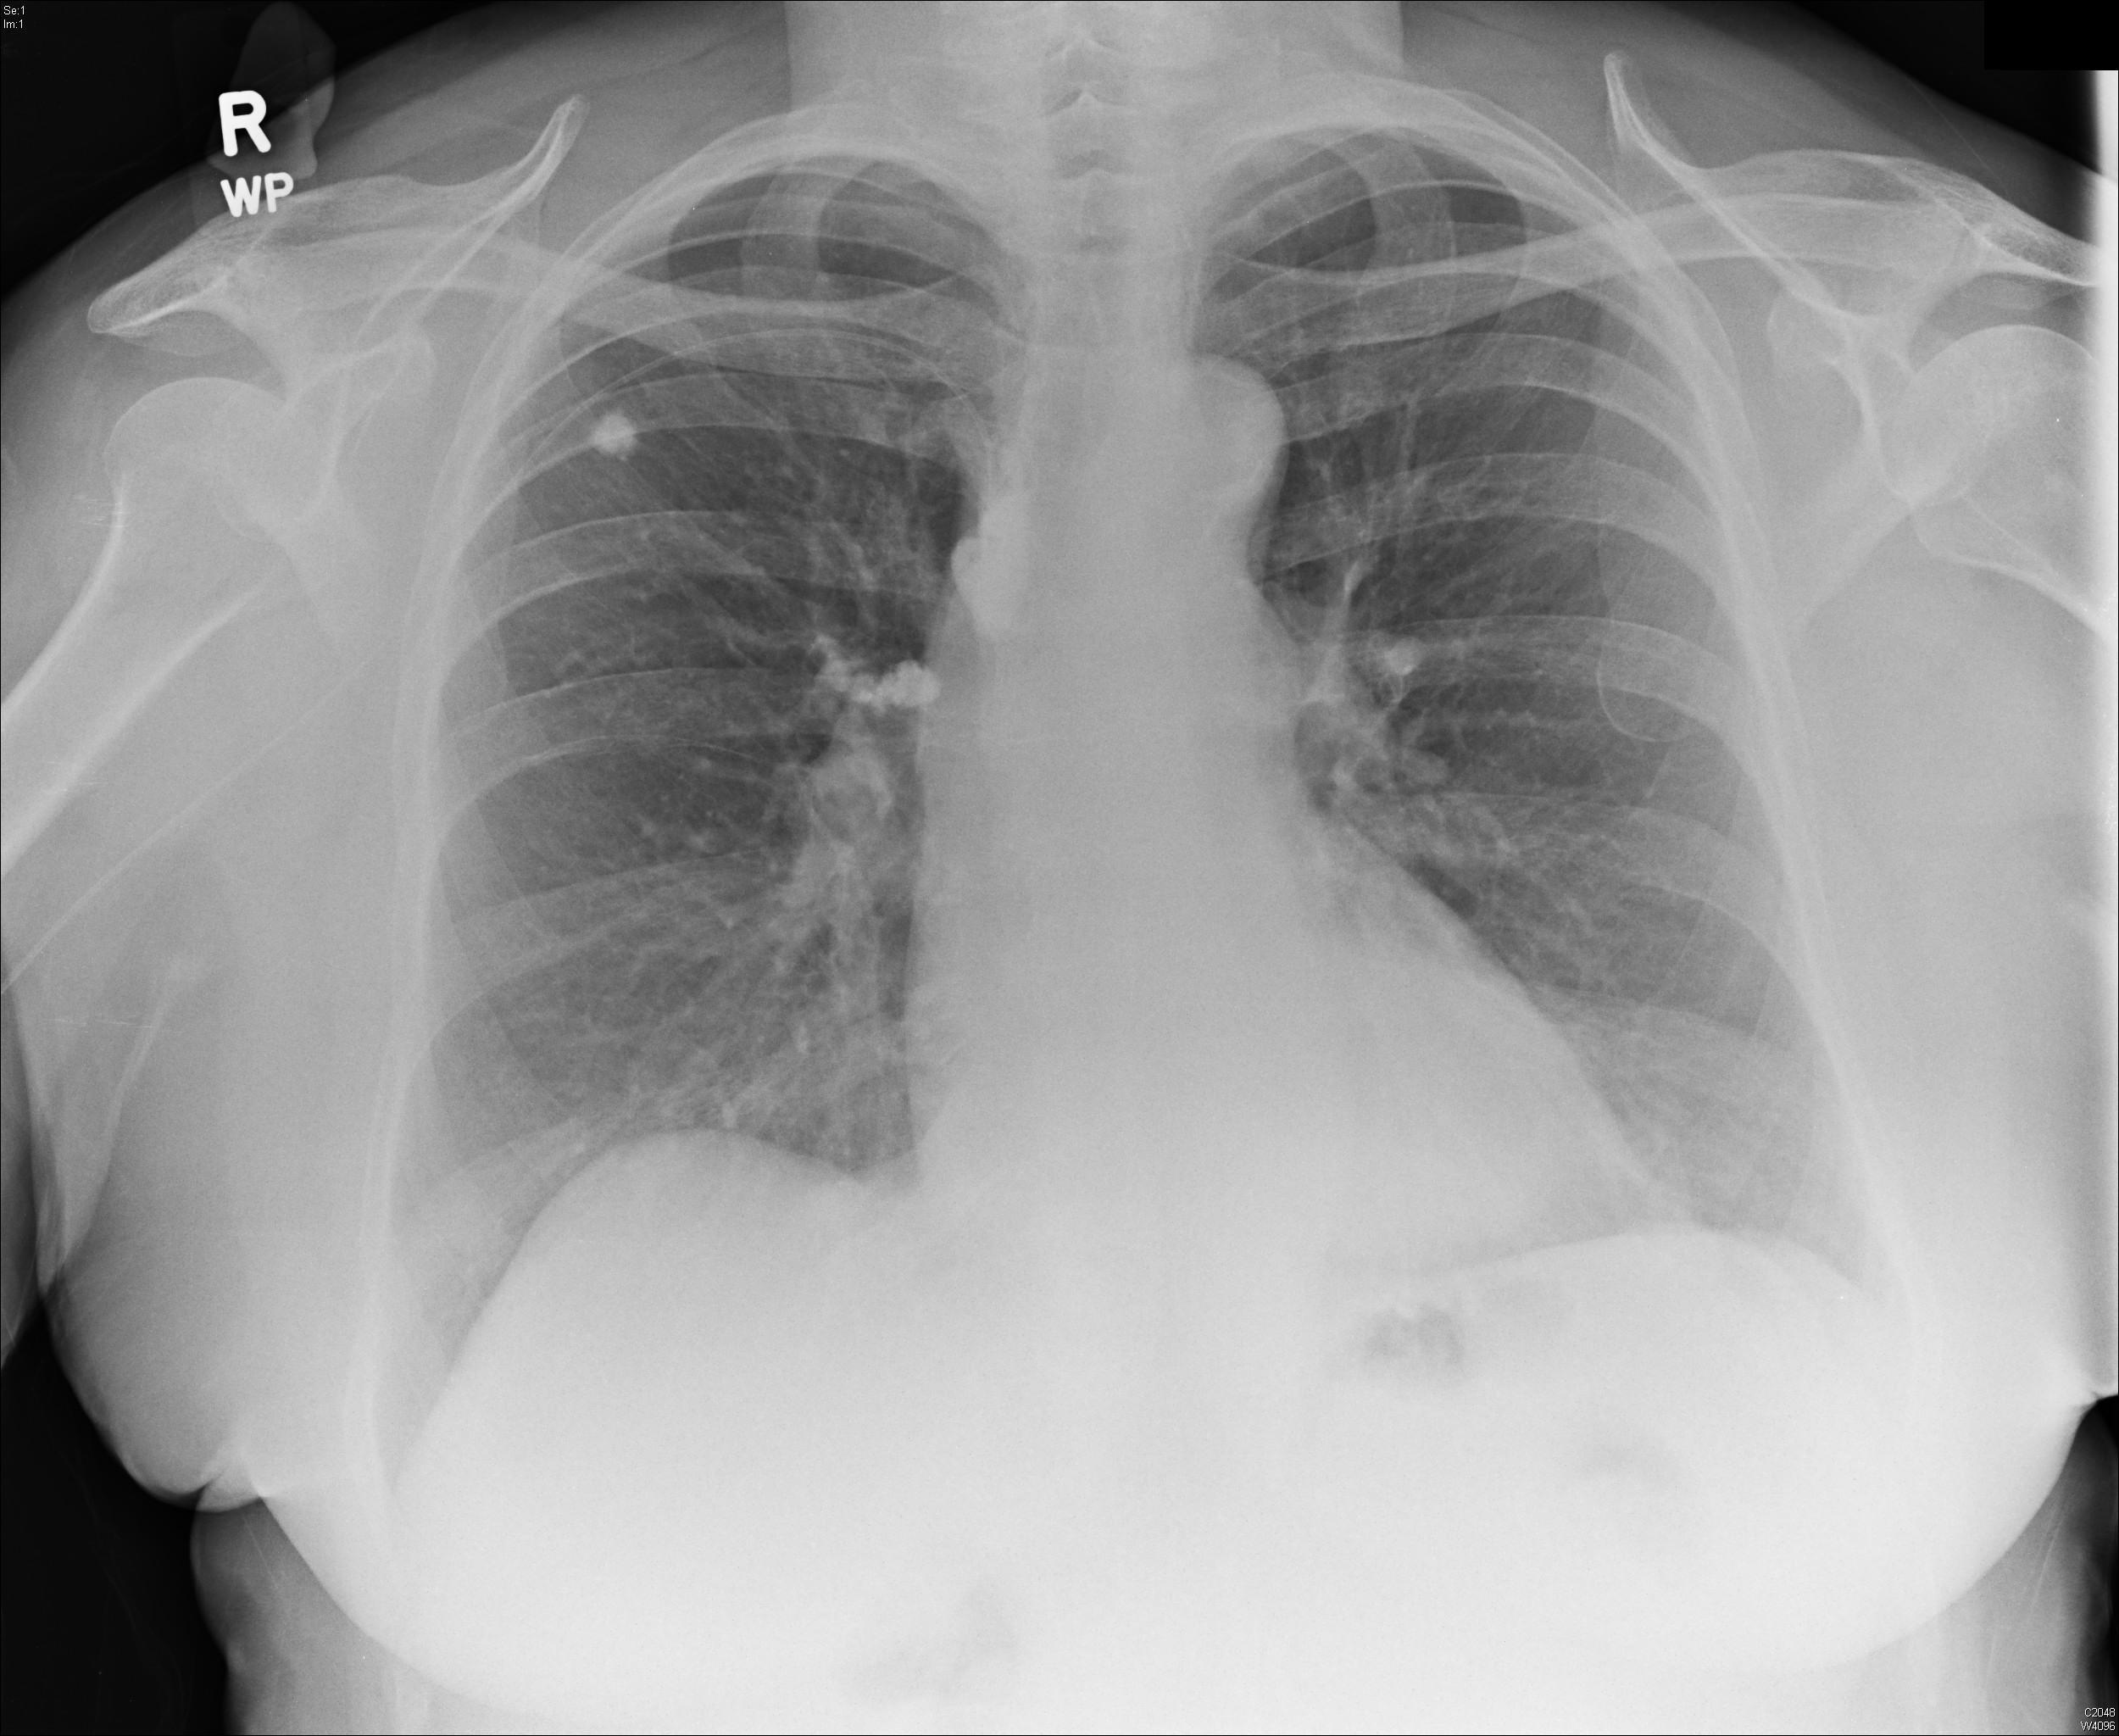

Old Tb Radiology . Chest radiographs are used to stratify for risk and to assess for asymptomatic active disease. Therefore, time from acquisition of infection to the development of clinical disease does not reliably predict the radiographic appearance of tb. In fact, the advances in molecular epidemiology in the 1990s have led to the discovery that the radiographic appearances of tb depends. Unfortunately, a history of infection with or exposure to tuberculosis may or may not be present, and evidence of active tuberculosis is present in less than 50% of cases. Sequelae of previous tuberculosis that is now inactive manifest characteristically as fibronodular opacities in the apical and upper lung zones. The list of possible causes include: Tb dna has been isolated from bone marrow, and it seems possible that bacteria remain dormant in the hypoxic environment of bone. Stability of radiographic findings for 6 months distinguishes inactive from active disease. Prior sarcoid prior exposure to silica dust Persons who have nodular or fibrotic lesions consistent with findings of old tuberculosis on chest radiograph and a positive tuberculin skin test. Old tb and other granulomatous conditions, e.g.

In fact, the advances in molecular epidemiology in the 1990s have led to the discovery that the radiographic appearances of tb depends. Stability of radiographic findings for 6 months distinguishes inactive from active disease. Chest radiographs are used to stratify for risk and to assess for asymptomatic active disease. Sequelae of previous tuberculosis that is now inactive manifest characteristically as fibronodular opacities in the apical and upper lung zones. Therefore, time from acquisition of infection to the development of clinical disease does not reliably predict the radiographic appearance of tb. Prior sarcoid prior exposure to silica dust The list of possible causes include: Persons who have nodular or fibrotic lesions consistent with findings of old tuberculosis on chest radiograph and a positive tuberculin skin test. Old tb and other granulomatous conditions, e.g. Unfortunately, a history of infection with or exposure to tuberculosis may or may not be present, and evidence of active tuberculosis is present in less than 50% of cases.

Pulmonary tuberculosis Radiology Cases Old Tb Radiology Persons who have nodular or fibrotic lesions consistent with findings of old tuberculosis on chest radiograph and a positive tuberculin skin test. Sequelae of previous tuberculosis that is now inactive manifest characteristically as fibronodular opacities in the apical and upper lung zones. The list of possible causes include: Stability of radiographic findings for 6 months distinguishes inactive from active disease.. Old Tb Radiology.

Pulmonary tuberculosis Image Old Tb Radiology Sequelae of previous tuberculosis that is now inactive manifest characteristically as fibronodular opacities in the apical and upper lung zones. The list of possible causes include: Stability of radiographic findings for 6 months distinguishes inactive from active disease. Persons who have nodular or fibrotic lesions consistent with findings of old tuberculosis on chest radiograph and a positive tuberculin skin test.. Old Tb Radiology.